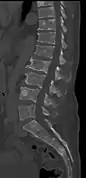

The diagnostic examination of a person with suspected multiple myeloma typically includes a skeletal survey. This is a series of X-rays of the skull, axial skeleton, and proximal long bones. Myeloma activity sometimes appears as "lytic lesions" (with local disappearance of normal bone due to resorption). And on the skull X-ray as "punched-out lesions" (raindrop skull). Lesions may also be sclerotic, which is seen as radiodense.[52] Overall, the radiodensity of myeloma is between −30 and 120 Hounsfield units (HU).[53] Magnetic resonance imaging is more sensitive than simple X-rays in the detection of lytic lesions, and may supersede a skeletal survey, especially when vertebral disease is suspected. Occasionally, a CT scan is performed to measure the size of soft-tissue plasmacytomas. Bone scans are typically not of any additional value in the workup of people with myeloma (no new bone formation; lytic lesions not well visualized on bone scan).

Pathological fracture of the lumbar spine due to multiple myeloma

CT scan of the lower vertebral column in a man with multiple myeloma, showing multiple osteoblastic lesions: These are more radiodense (brighter in this image) than the surrounding cancellous bone, in contrast to osteolytic lesions, which are less radiodense.